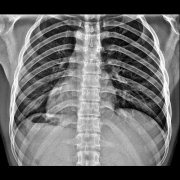

拍摄胸片时常用的拍摄站位

拍摄胸片时,常用的拍摄站位主要包括以下几种,有何不同呢?让我们一起来看一下吧! 1. 后前位(正位) 站位:被摄者站立,前胸壁紧贴片盒支架,两手背放在髋部上方,两肘内旋,...更多 -